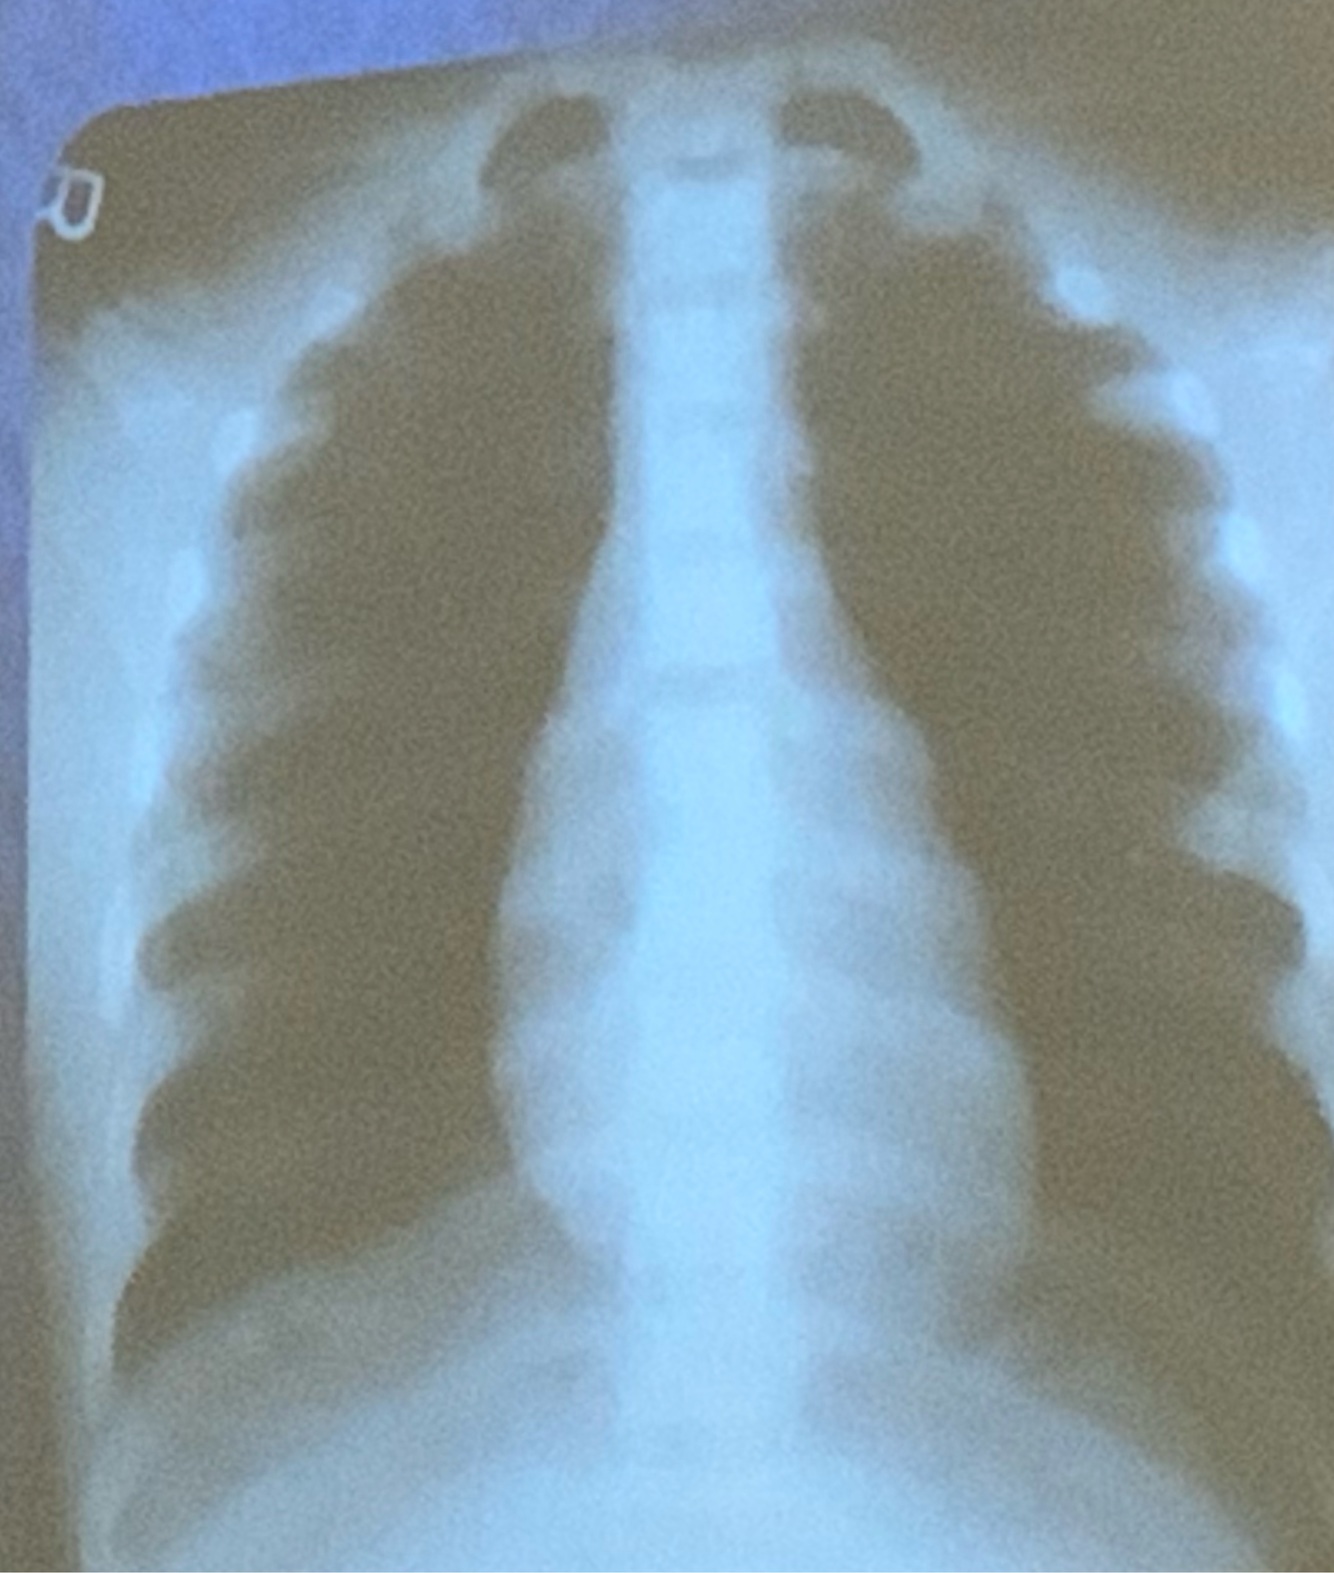

Dx

Derrame pleural